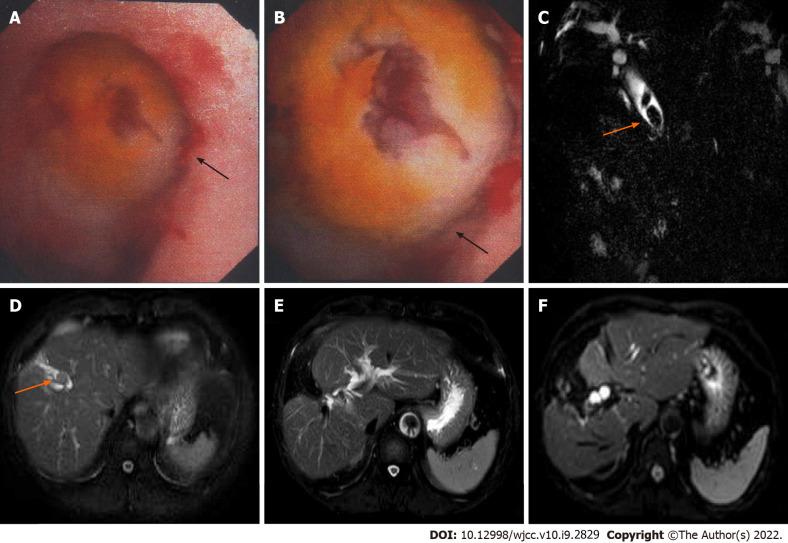

The patient was a 69-year-old male who presented with intermittent right upper abdominal pain for one month and 4-pound weight loss before admission. Abdominal magnetic resonance imaging and magnetic resonance cholangiopancreatography showed multiple stones in the bile ducts accompanied by dilatation of the intrahepatic and extrahepatic bile ducts. The preoperative diagnoses were right intrahepatic bile duct stones and extrahepatic bile duct stones; thus, surgical resection was performed. Choledochoscopy showed that the bile duct wall of the right anterior lobe was thickened, and a mass was visible in the duct. Then, a biopsy was performed, and rapid frozen-section biopsy analysis indicated that the tumor was malignant. The final diagnosis was SICC (T1aN0M0). Huaier granules were taken by the patient as anticancer therapy after surgery. The patient attended follow-up for 72 mo with no tumor recurrence or metastasis.

https://cdn.ncbi.nlm.nih.gov/pmc/blobs/906e/8968806/4021306a8d8e/WJCC-10-2829-g001.jpg